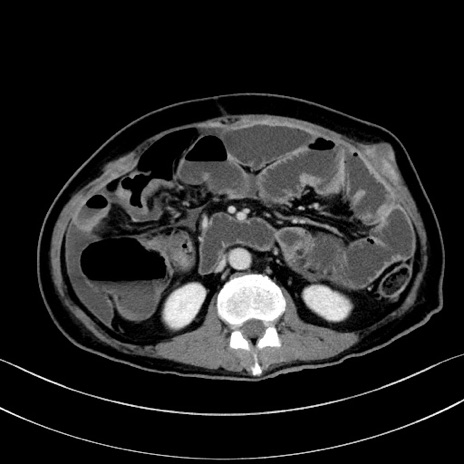

冠状断像

【症例】60歳代男性

【主訴】嘔吐

【現病歴】胃癌にて胃全摘後。食思不振が悪化し、夜中に嘔吐することがある。

【既往歴】胃癌、胃全摘、脾摘、胆摘後

【データ】WBC 5900、CRP 10.56